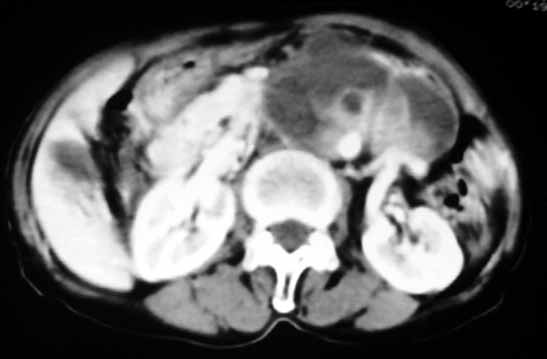

以下是引用天南地北在2007-4-30 17:42:00的发言:[br]增强扫描显示腹主动脉给包绕、推移。肿块不规则强化,[br]修正我在平扫的诊断[br]支持考虑:间叶源性肿瘤可能性大

以下是引用余辉在2007-4-30 18:01:00的发言:[br]病灶前方的条状增强影是什么?若是胰腺,位置似乎有点低,若是十二指肠,似乎又不诫该是那样强化,姑且将其看作胰腺吧,那么考虑来源于胰腺粘液囊腺瘤可能性大,其次考虑来源于肠系膜或者后腹膜的肿瘤如平滑肌肉瘤,异位嗜铬细胞瘤及淋巴瘤等。

以下是引用zyx168在2007-4-30 23:24:00的发言:[br]考虑:间叶源性肿瘤可能性大